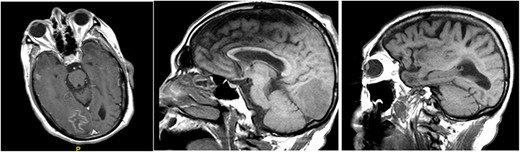

Magnetic resonance imaging (MRI) of brain, with and without contrast, identified four enhancing lesions, concerning for intracranial metastatic disease, located in the right temporal, occipital and frontal lobes (Fig. 1), as well as one in the right cerebellum. The largest mass was in the right cerebellum and measured approximately 3 cm × 2.7 cm. There was associated edema throughout the right occipital and temporal lobes without significant mass-effect or midline shift. The patient’s chest, abdomen and pelvis CT were negative for any malignancy. Neurosurgery was consulted to perform a brain lesion biopsy.

MRI of brain, with and without contrast, identified four enhancing lesions, concerning for intracranial metastatic disease, located in the right temporal (left), occipital (center) and frontal lobes (right).